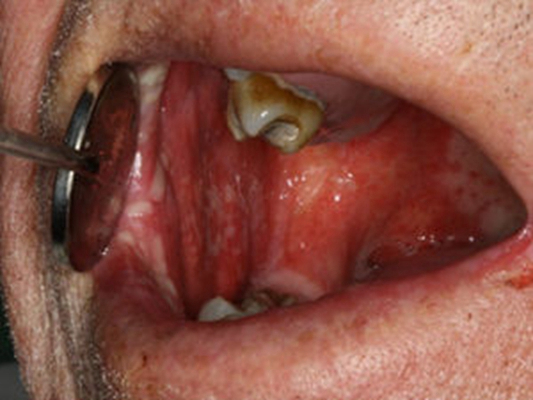

咽喉炎圖片

咽喉潰瘍 (9)